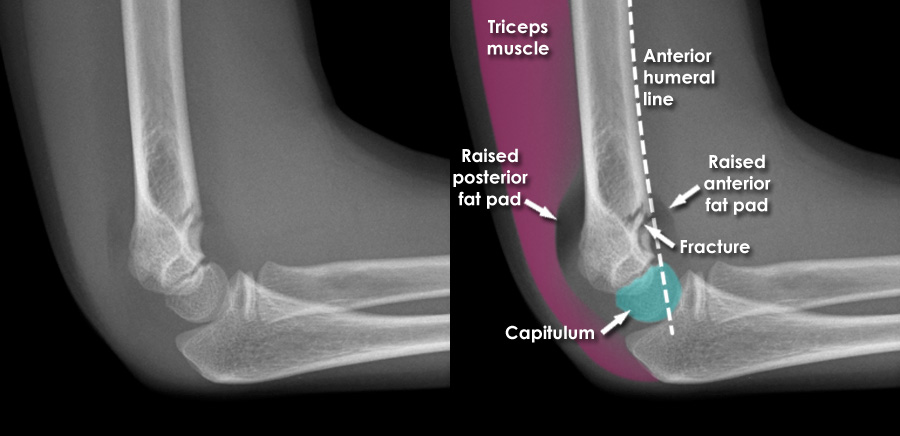

humeral line anterior elbow supracondylar pediatric fractures normal radiology fracture humerus radiopaedia capitellum angle capitulum joint case types injuries occult

elbow forearm normal lateral alignment anterior capitellum radiograph interpreting radiographs fracture supracondylar intersect

elbow humeral fracture supracondylar forearm capitellum radiographs interpreting intersect

elbow pad fat normal anterior pediatric injuries sign

radiopaedia line humeral anterior radiology

elbow fracture humeral fractures capitellum humerus radiology pediatrics canadiem unfall lkh wiener neustadt

humeral anterior line pediatric fracture abnormal pedia

elbow lateral paediatric raised wikiradiography anterior there supinator arrow signs

capitellum dislocation elbow pediatric through drawn lateral anterior humeral pass should line

Anterior humeral line. Pediatric humeral fracture. Elbow injuries